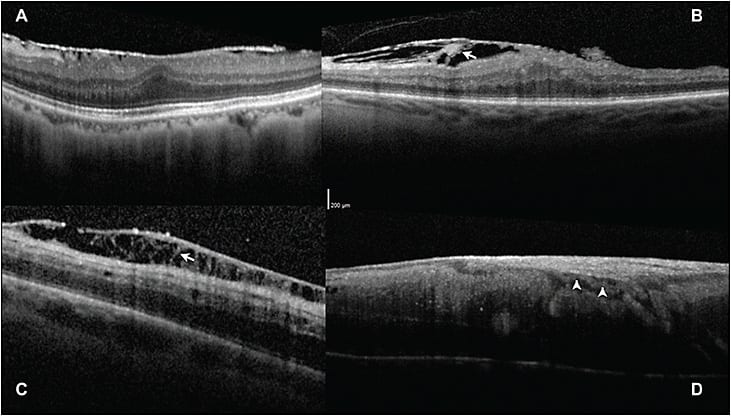

Using angiography and intraoperative Doppler SD-OCT in its early stages, we identified this lesion as RAP and chorioretinal anastomosis (ie, a neovascular process).11 This lesion is present in roughly 20% of children with early Coats disease, further supporting the use of anti-VEGF therapy, and it is demonstrated in Figure 3.

Figure 3. Multimodal imaging in retinal angiomatous proliferation and chorioretinal anastomosis in childhood Coats disease. A) Widefield intraoperative angiography in a child with Coats disease with typical chorioretinal anastomosis and PED characteristic of type 3 choroidal neovascularization (arrow). B) Retinal vessels (arrow) disappearing into the fovea of a patient with Coats disease on SD-OCT. C) Doppler overlay demonstrating chorioretinal anastomosis (arrow) and choroidal neovascularization. D) Additional Doppler SD-OCT in patient with Coats disease and chorioretinal anastomosis (arrow). Images obtained with Heidelberg OCT and Bioptigen Doppler OCT (Research Triangle Park, NC).